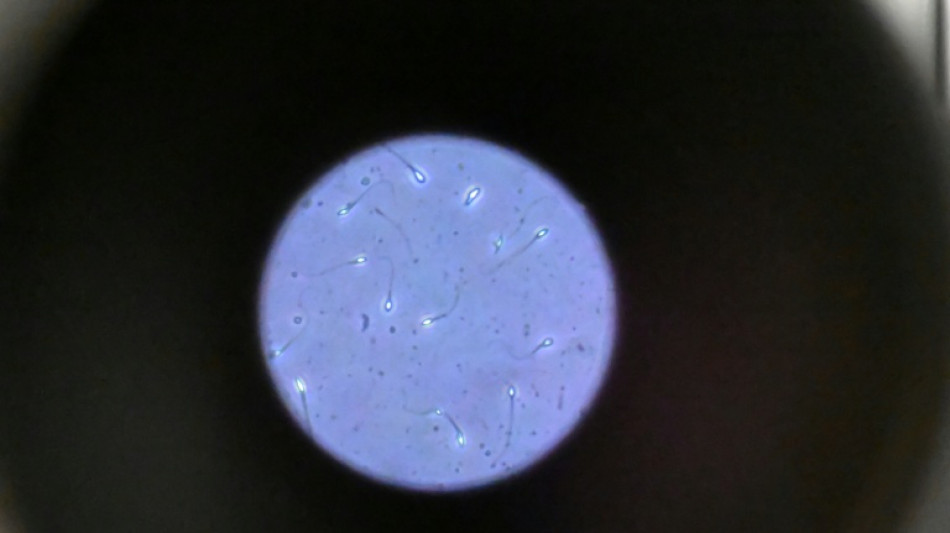

Les chercheurs ont testé successivement du sperme de souris et humain dans ce dispositif placé dans un appareil en constante rotation pour simuler la microgravité.

Les gamètes ont été environ 50 % moins performants pour naviguer à travers ce parcours que sous la gravité terrestre. Cela équivaut à une baisse de 30% du taux de fécondation réussie, selon les résultats de l'étude.

Les spermatozoïdes ayant réussi à franchir le parcours semblaient produire des embryons de meilleure qualité.

Il semble que le stress lié à la microgravité ait agi comme un "filtre" éliminant les plus faibles et "ne laissant en lice que les plus performants", ce qui pourrait s'avérer "bénéfique", selon Mme McPherson.